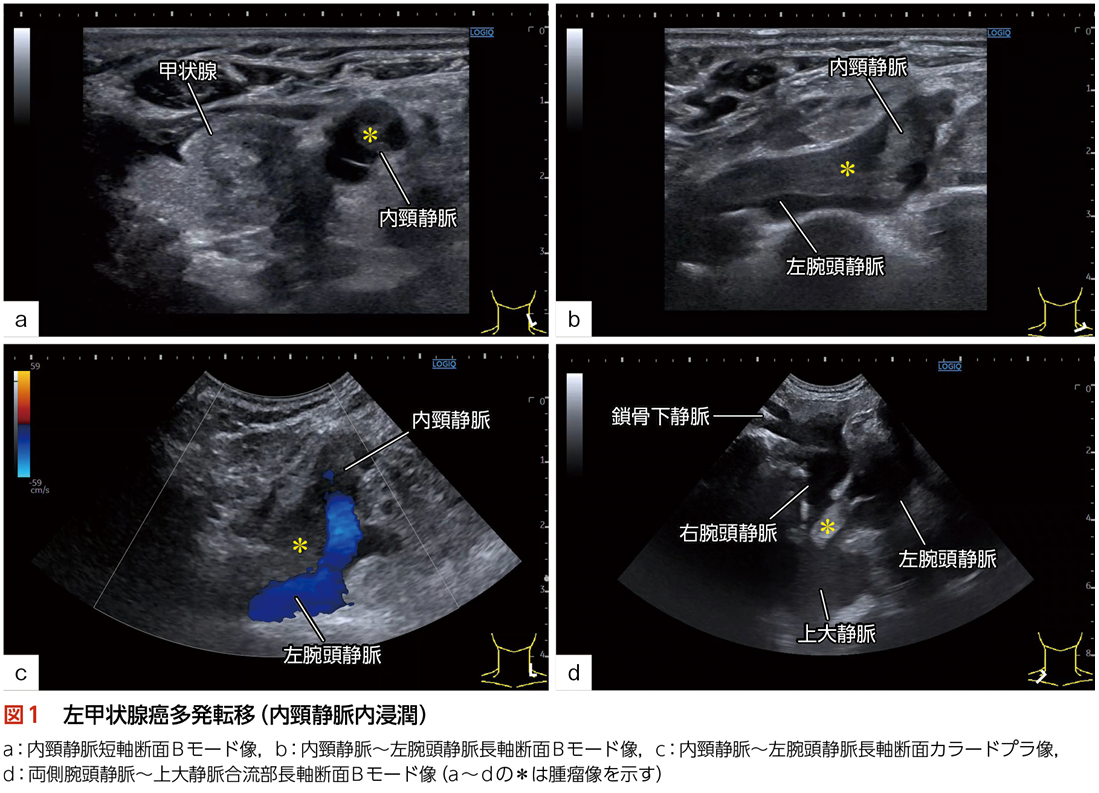

◆検査目的:副甲状腺機能亢進症疑いにて甲状腺エコーを実施した際,内頸静脈内に腫瘤像が観察されたため,頸静脈エコー検査が追加された